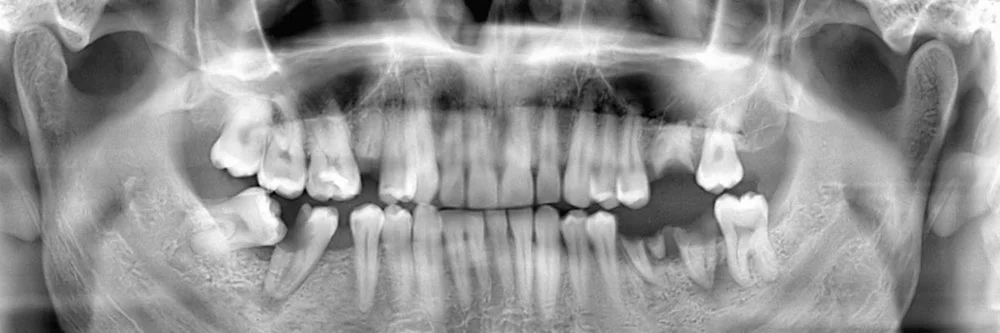

You may need a wisdom teeth extraction at some point. It is rare for a person to have enough room for all of their wisdom teeth, and as a result, they tend to grow in impacted. This can be uncomfortable, push your other teeth forward, and create a space for food to become trapped, increasing your risk of infection and decay. This is why we often recommend that our Hillcrest, CA patients have their wisdom teeth removed. When you schedule an appointment with Bella Vita Dental of Hillcrest, we can examine you, take x-rays, and let you know if and when you should schedule an extraction procedure. You can reach us by calling (619) 650-6395.

If your wisdom teeth have grown in straight, removing them is fairly easy. In this case, you would visit a 92103 dentist to have them pulled out using dental tools. Most likely, no surgery would be required. However, if your teeth are impacted, the procedure requires oral surgery. In order to access the actual tooth, the gum tissue covering it will need to be cut open. After numbing the area, a flap will be created in the gum tissue. This allows the dentist or oral surgeon to view the tooth. If muscle or bone is covering it, that will also need to be cut away to provide clear access to the actual tooth. At this point, your Hillcrest dentist may be able to grab the tooth and simply lift it out of the socket. If, however, it does not budge when being wiggled; the actual tooth will need to be broken into several pieces that can be extracted individually.